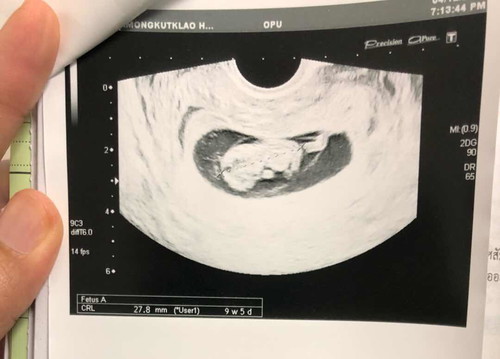

2014/12/04 9W5D

?ความน่ารักกำลังฉายแววแล้วจ้า? #วันนี้ 2019/12/18 คุณหมอนัดรอบที่ 2 ในเวลาไปฟังผลเลือดกับรายละเอียดการตรวจครั้งที่แล้ว และก็มีตรวจท้องนิดหน่อยแต่ไม่ได้ซาวนะเพราะซาวไปแล้ว ผลคือปกติ :) ✨#รอบหน้าไปพบหมอนอกเวลาคาดว่าจะได้อัลตร้าซาวอีกครั้ง #มีแม่ๆคนไหนนอนไม่หลับบ้างคะ นับแกะก็แล้ว นับดาวก็แล้ว 1-100 ก็นับแล้ว นิทานก็ฟังเเล้ว การ์ตูนก็ดูแล้ว นอนไม่หลับสักที

กำลังตั้งครรภ์